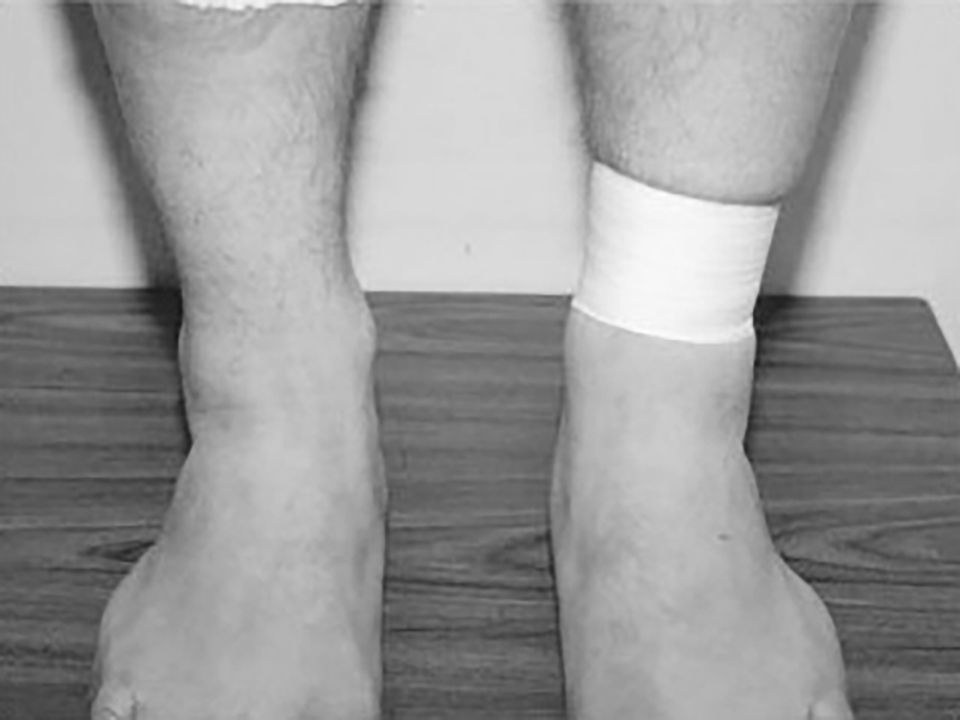

Stabilization test (Figure 8)

Amendola has described the “stabilization test,” [21] which can be useful to confirm diagnosis during the subacute or chronic phase of injury once acute swelling and pain have subsided. This test is performed by tightly applying several layers of 1.5-in athletic tape just above the ankle joint to stabilize the distal syndesmosis. The patient is then asked to stand, walk, and perform a toe raise and jump. The test result is positive if these maneuvers are less painful after taping.